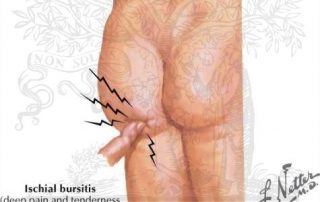

Ischial Bursitis

There are two types of hip bursitis. Ischial Bursitis which is a swollen bursa near where your hamstring attaches on your Ischial Tuberosity (SITS bone) and Trochanteric Bursitis which is where your [...]